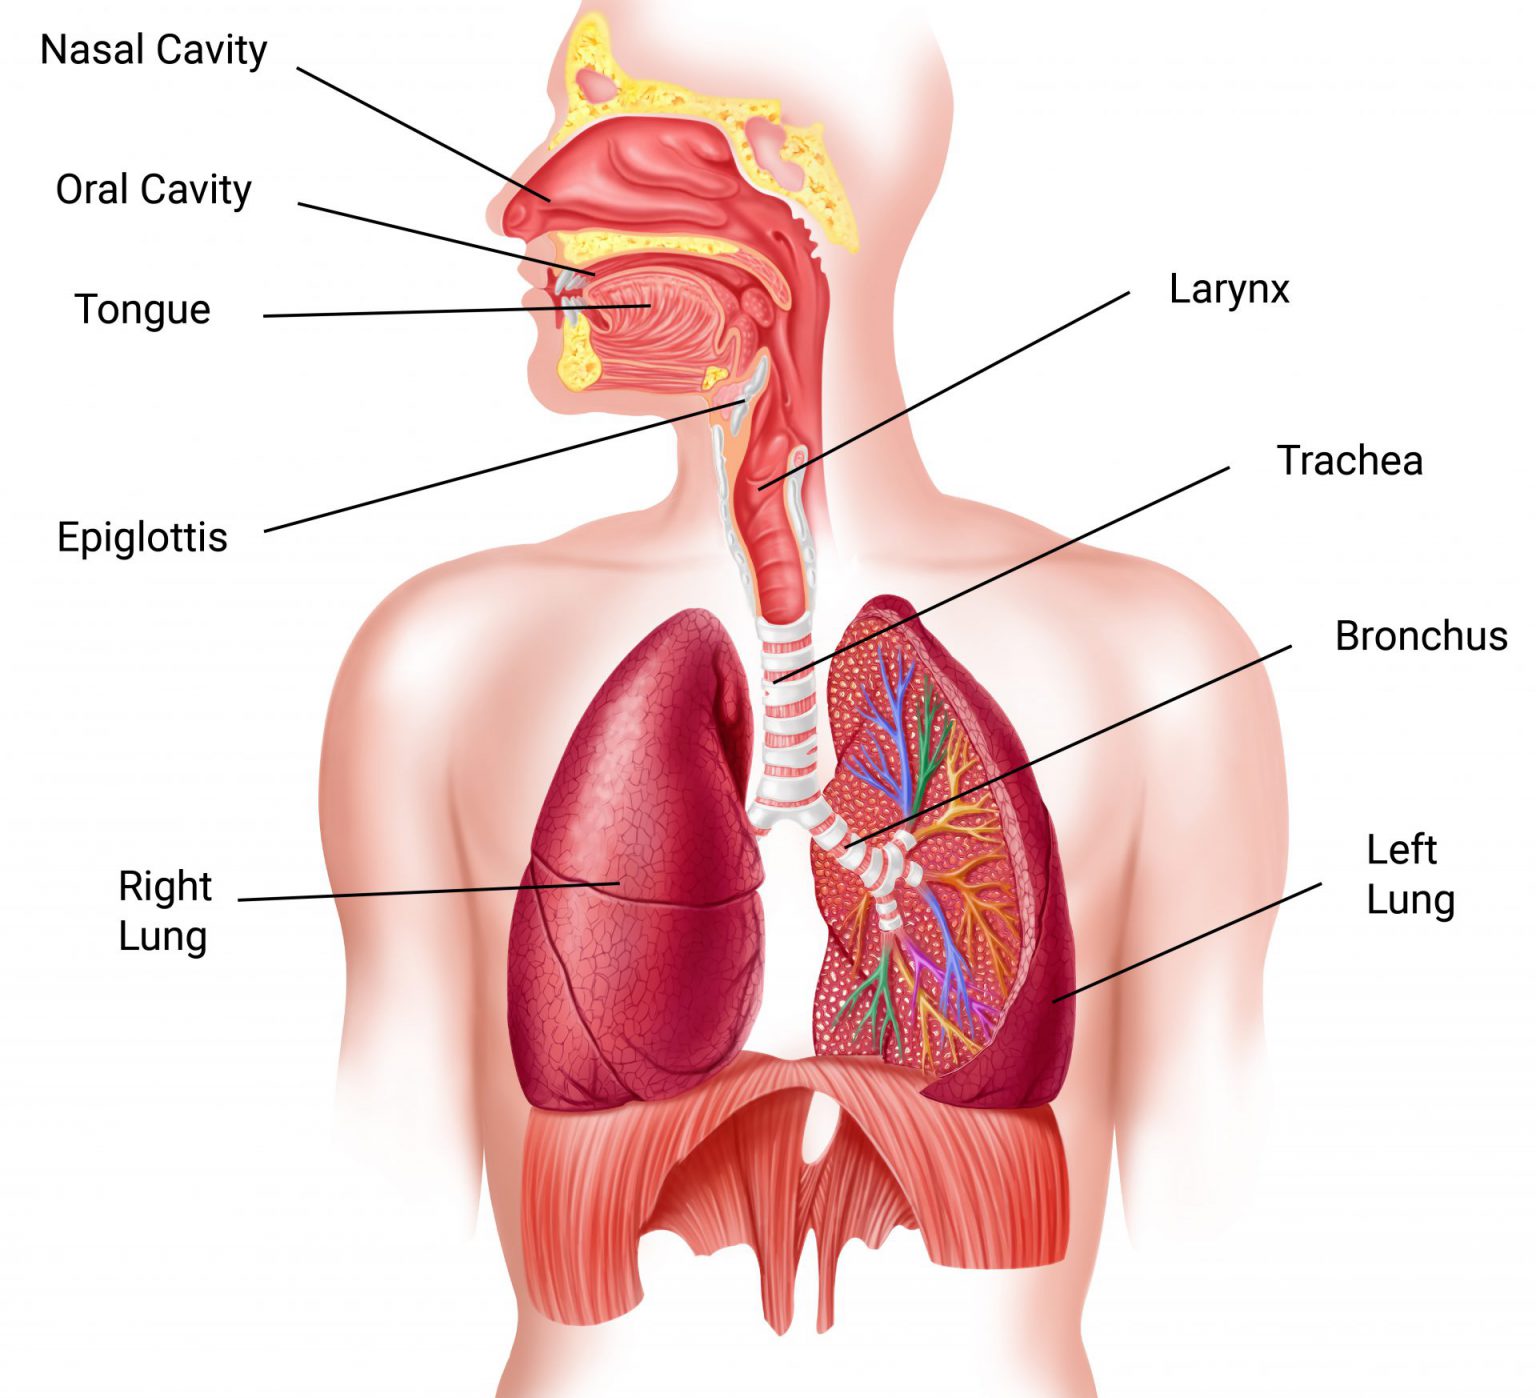

Таинство дыхания: глубокий взгляд на легкие человека в картинках

Раздел: Снимки-откровения